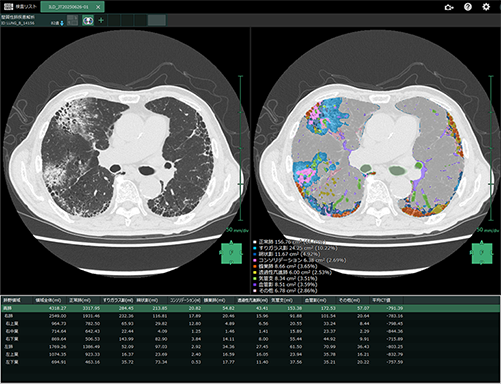

胸部CT画像から、異常所見が疑われる領域を性状ごとに分類し、それぞれの体積・面積や全体における割合を自動的に算出することで、間質性肺疾患の診断を支援します。